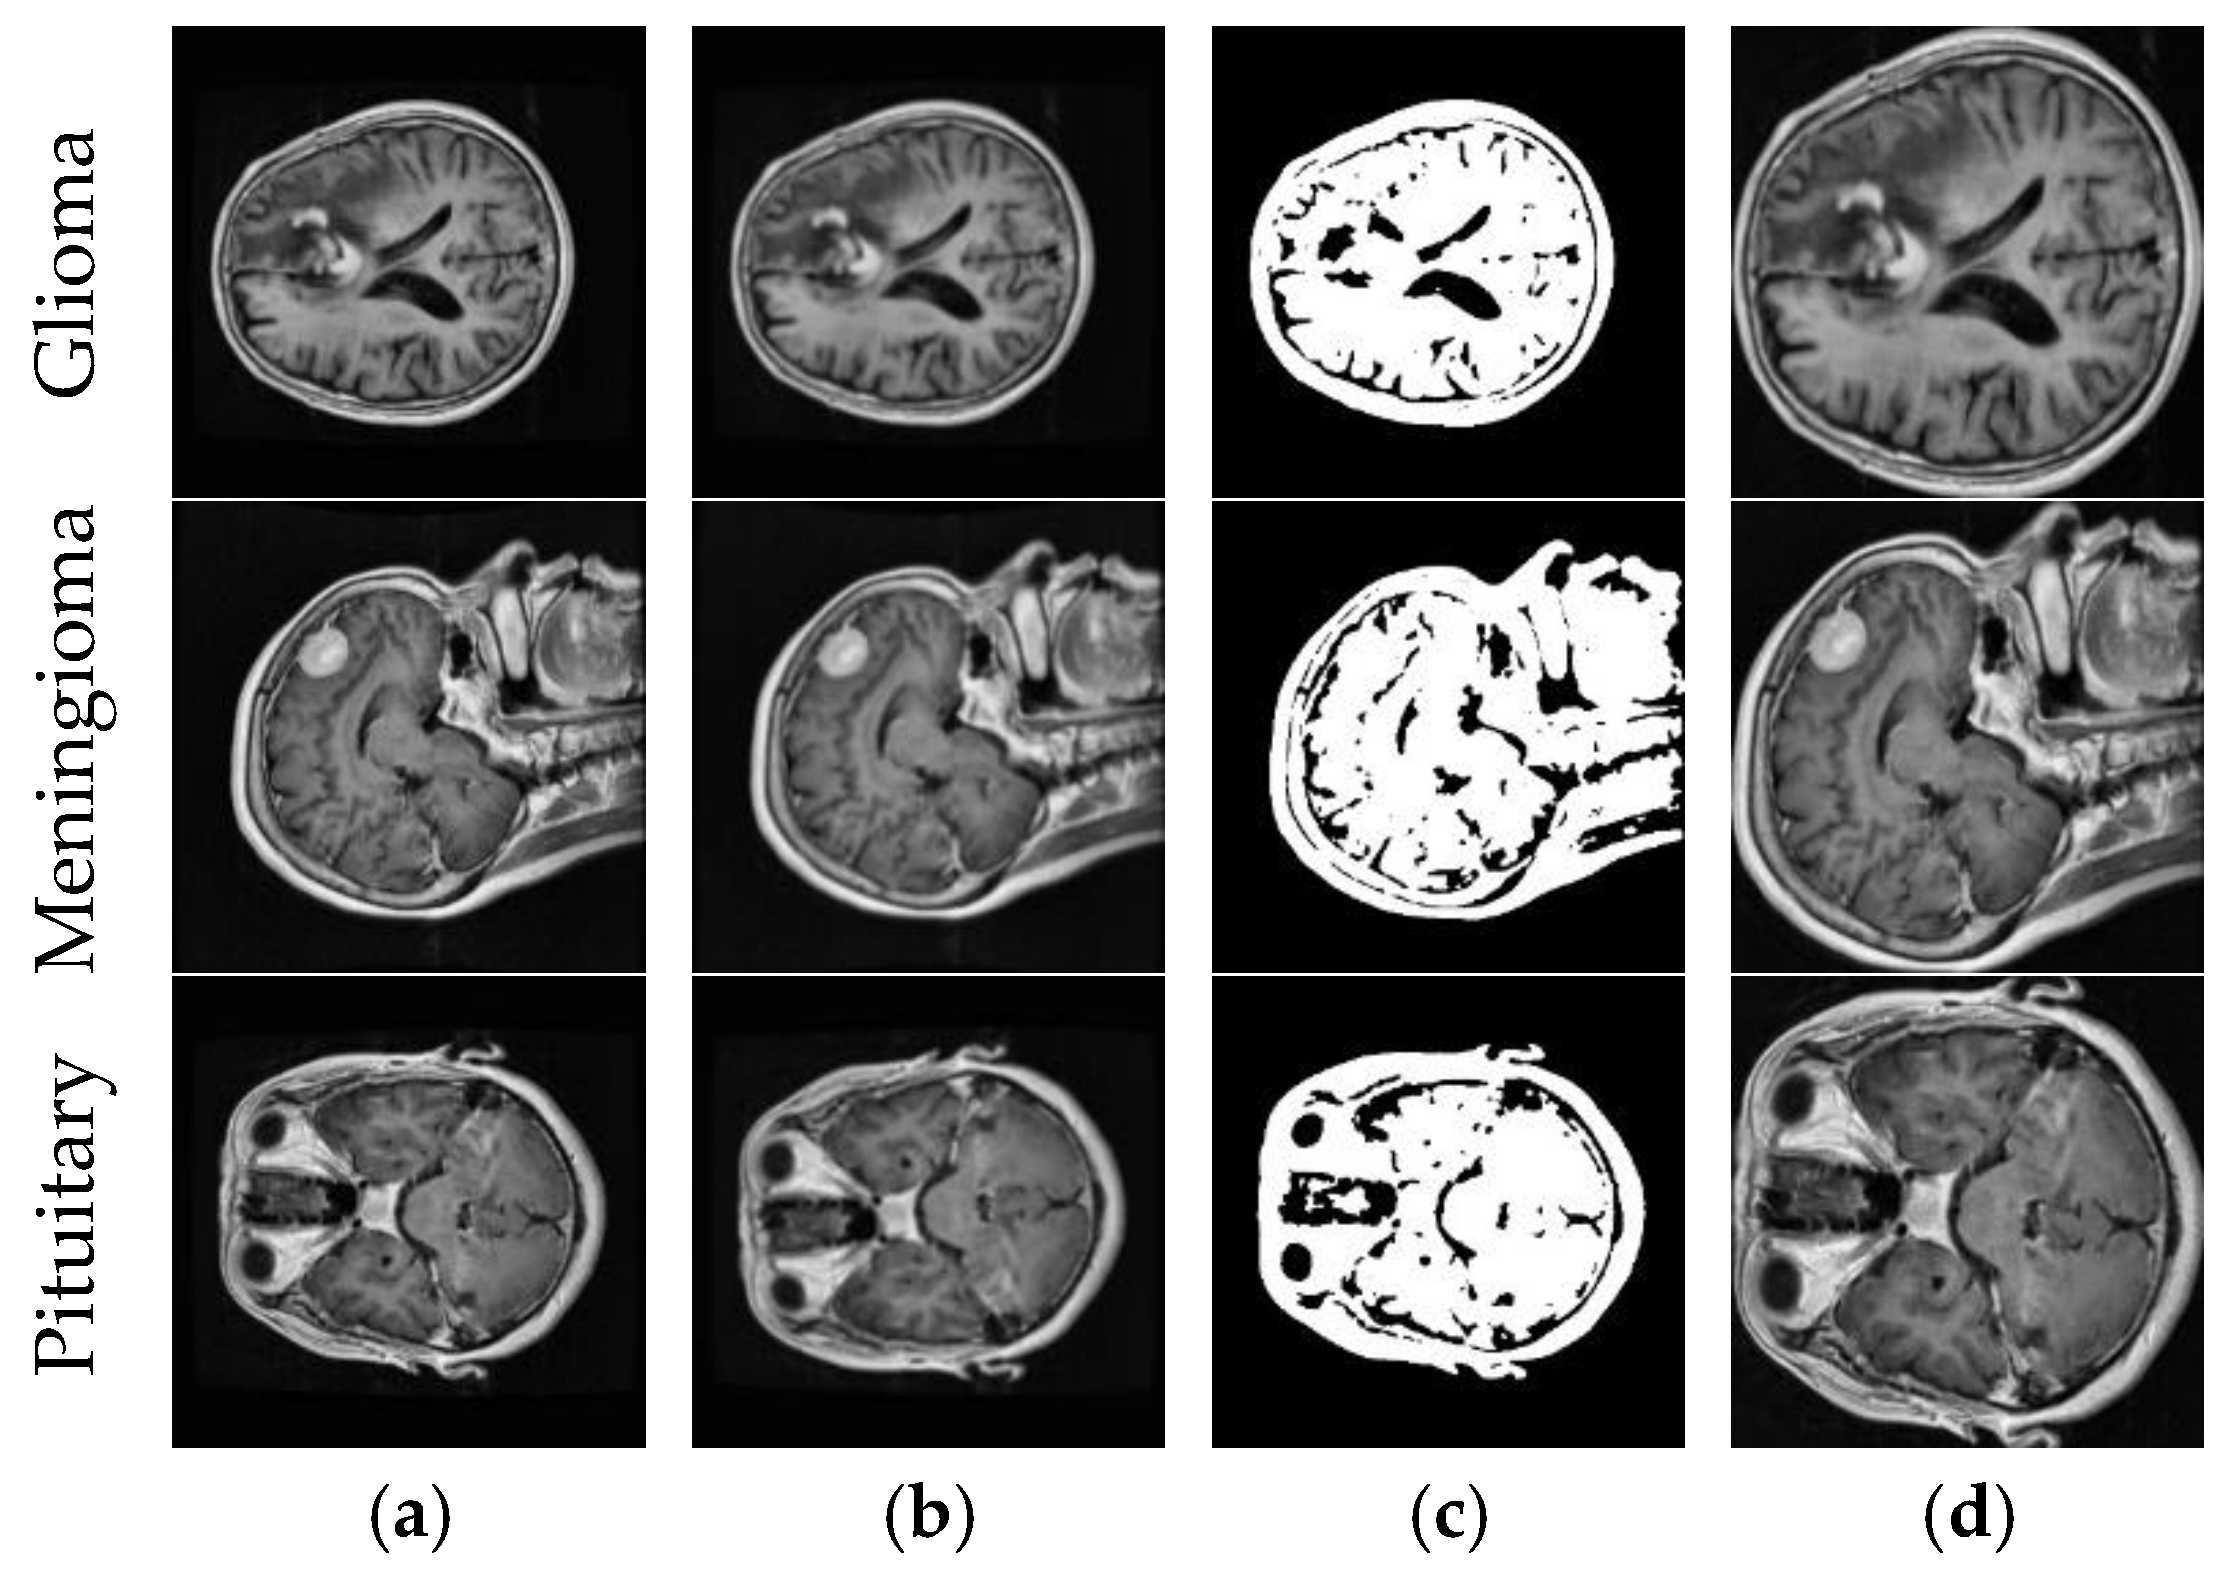

We divided the datasets into train, validation, and test. First, we split the datasets into 80% train and 20% test. Then, we split 10% of the training datasets into validation. Figure 2 shows example MR images of brain tumor types and the process of the image segmentation algorithm.

Figure 2.

Brain tumor types and the process of the image segmentation algorithm. (a) Original image; (b) Gaussian blur with a 9 × 9 kernel; (c) binary image-otsu thresholding; (d) final image.

The MRI images were first preprocessed. In Figure 2, a noise outside the brain region was removed. For CNN architectures to focus only on the brain region, we first applied Gaussian blur with the 9 × 9 kernel and then applied Otsu thresholding to extract the binary image. The brain region’s contours were detected in the binary image, and brain region segmentation was performed based on the extreme points of the largest contour in all directions. Thus, CNN architectures will only operate within the brain region in real-time applications.